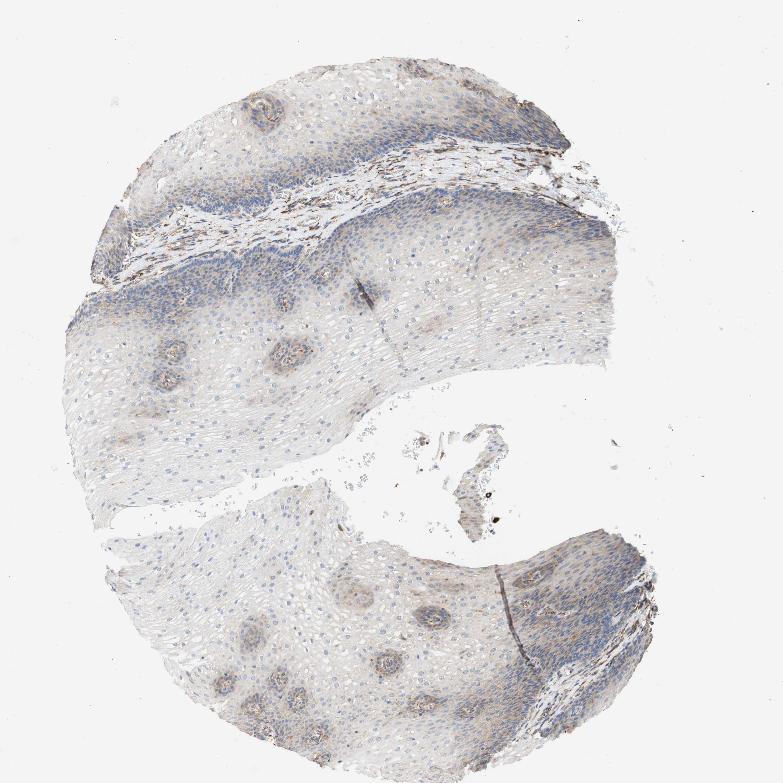

ESOPHAGUS - Antibody stainingi

Antibody staining in the annotated cell types in the current human tissue is reported as not detected, low, medium, or high, based on conventional immunohistochemistry profiling in selected tissues. This score is based on the combination of the staining intensity and fraction of stained cells.

Each image is clickable and will lead to virtual microscopy that enables deeper exploration of all samples and also displays staining intensity scores, fraction scores and subcellular localization as well as patient and tissue information for each sample.

Antibody HPA011811

Squamous epithelial cells Low